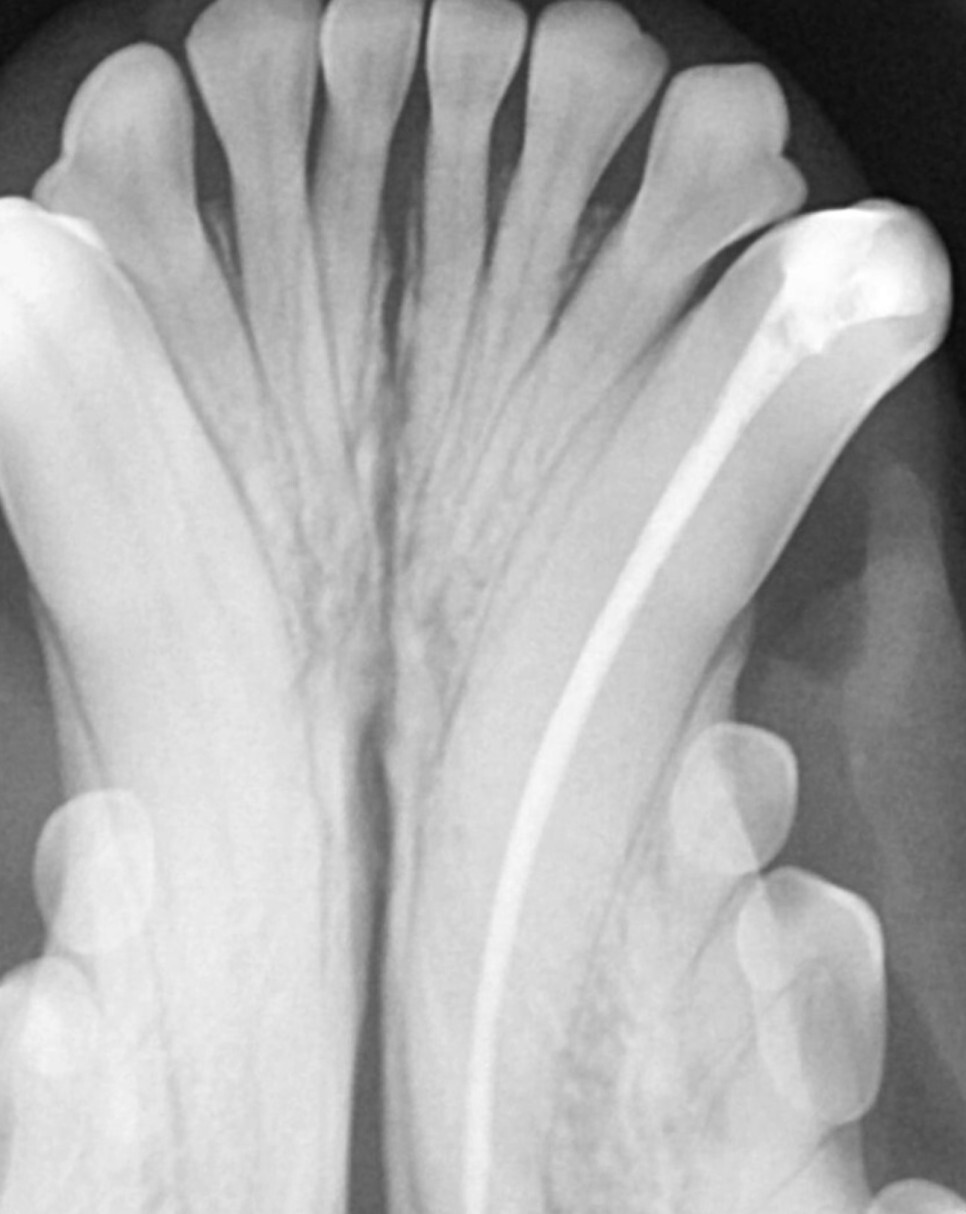

근관치료는 감염된 치수를 제거하고 충진 재가

잘 들어갈 수 있도록 근관을 형성, 소독 후

생체 친화적인 물질을 이용하여 치수강을 채워

밀봉하는 순서로 진행합니다.

치아 내부 공간이 워낙 협소하다 보니

세밀하고 섬세한 스킬이 요구되는 치료입니다.

강아지의 치아, 특히 송곳니는 사람보다 훨씬 길기

때문에 동물용으로 제조된 재료를 사용할 수밖에

없습니다.

치료 이후에는 감염의 징후가 있는지 확인을

위해 6개월~1년 후에 치과 방사선 촬영이 필요합니다.